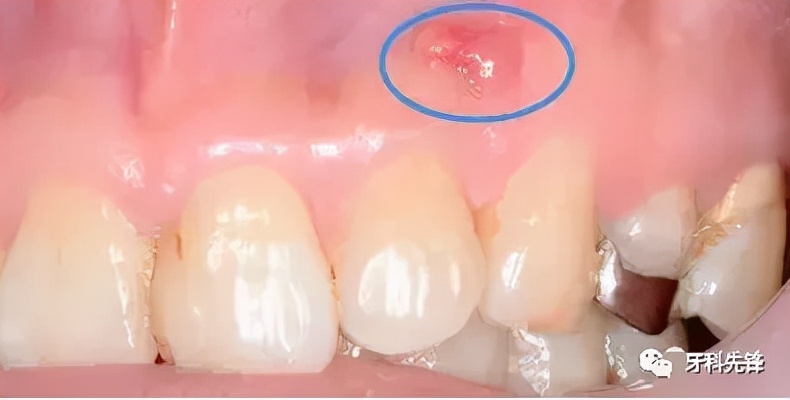

只是个小包包吗?其实并没那么简单!你看到的只是表面现象,长脓包说明牙龈内的牙根已经发炎,细菌感染牙髓演变成牙根炎症,引起牙槽骨蔓延,牙槽骨遭到炎症影响,所以牙龈上才会鼓起一个脓包,从根尖到牙根的瘘管,脓包内产生的分泌物由此流出。而出现这种问题就必须去看牙医了,否则情况就会越来越严重。

当蛀牙蛀到牙髓的时候,细菌感染了牙髓后逐渐繁殖,炎症通过牙髓进而发展大牙根、牙槽骨然后再开始慢慢蔓延,牙槽骨遭到破坏,吸收,便会在牙龈上鼓起一个脓包,形成从根尖到牙根的瘘管,炎症产生的分泌物便由此流出。